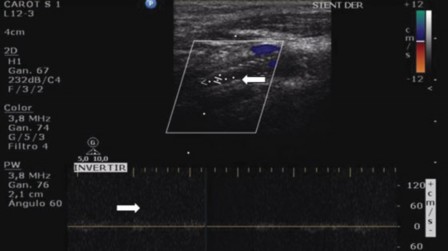

Zhou W y col., en cambio, definen como criterio fiable para el diagnóstico de reestenosis superiores al 70% un pico sistólico de 300 cm/seg.19 En caso de oclusión del stent se debe documentar su existencia. Para ello empleamos los mismos criterios, realizando registros en modo B, Doppler color y espectral. En las obstrucciones agudas se observa la presencia de un trombo hipoecoico, que ocupa la totalidad de la luz vascular, y de aspecto globuloso. Hacia la fase crónica aumenta la ecogenicidad del trombo y disminuye el calibre del vaso. Por último, la oclusión se va a manifestar con ausencia de flujo tanto al examen Doppler color como espectral (►Figs. 10 y 11).

EDC donde se observa ausencia de flujo en el mapa color dentro del stent (flecha).

EDC y espectral donde se observa ausencia de flujo tanto en el mapa color como en el Doppler espectral (flechas).